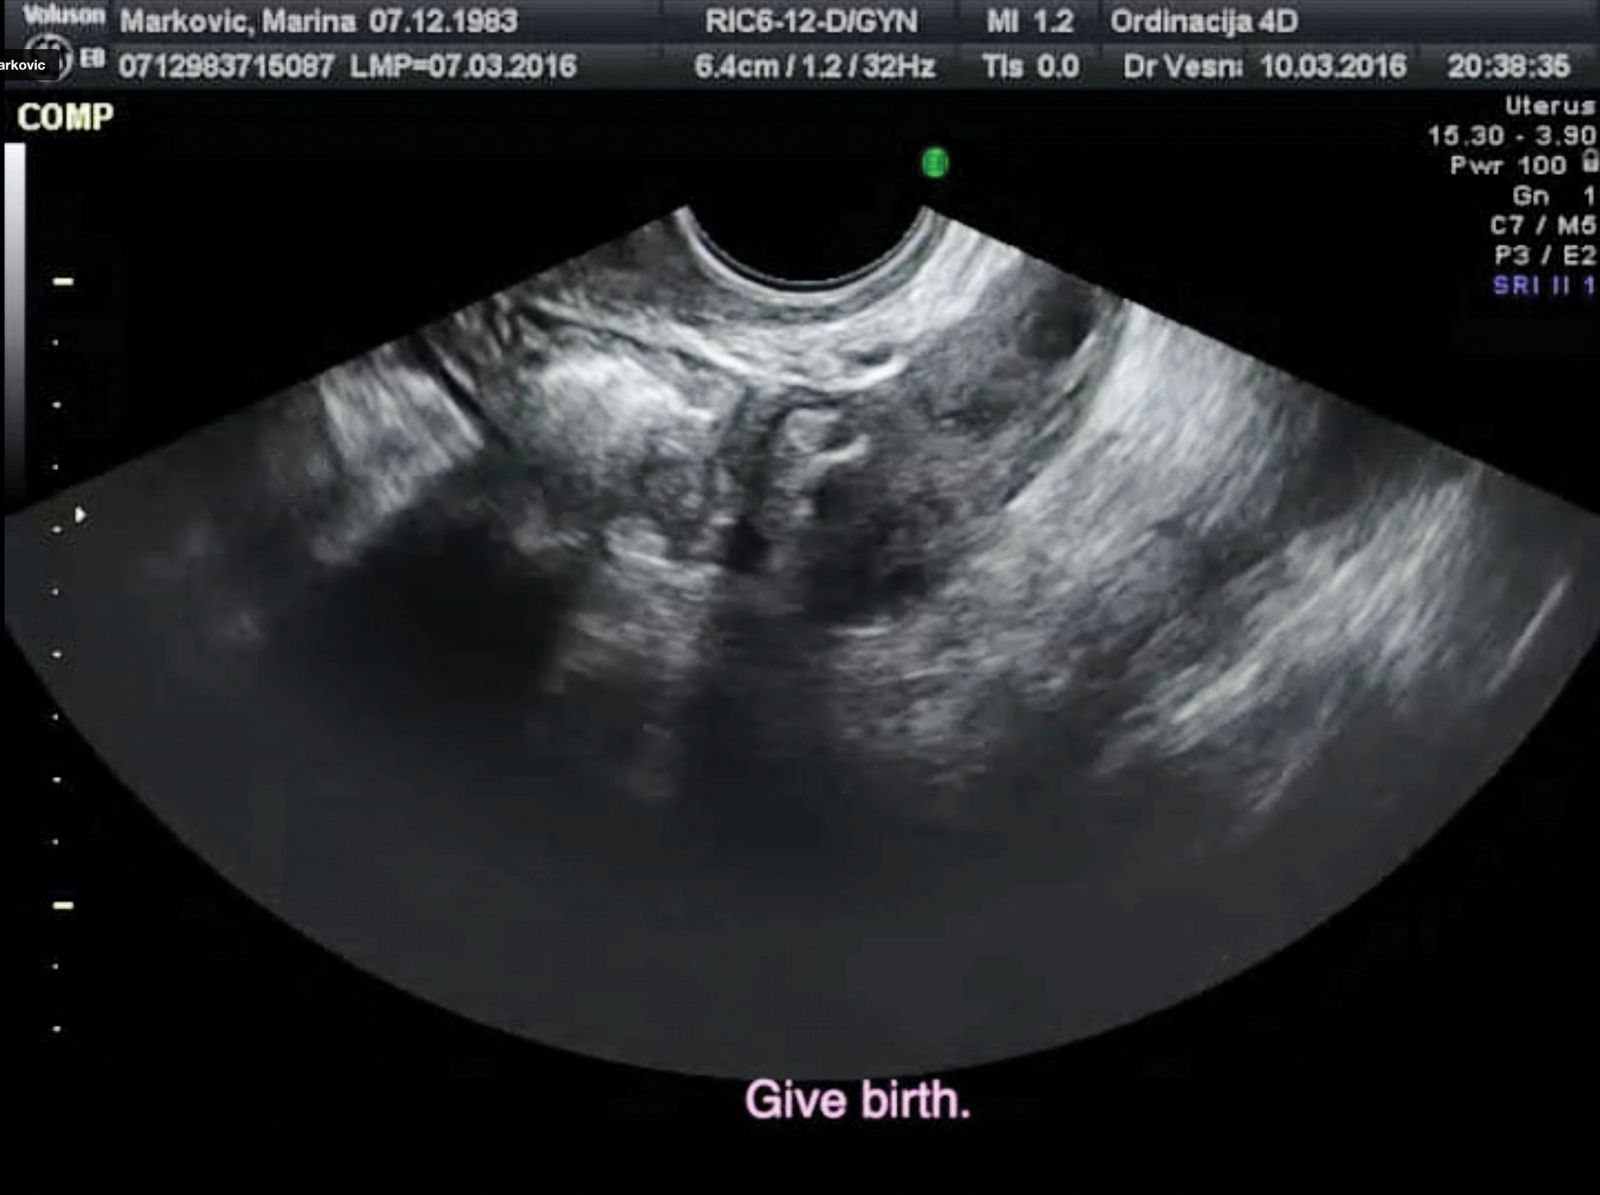

In Void, ki ga je posnela srbska filmarka Marina Marković, izgleda kot lekcija iz altmanskega overlappinga: na ekranu vidimo le rentgenski posnetek maternice, čez to pa se gnetejo, trejo in prehitevajo prekrivajoči se glasovi starejših žensk, ki mlajšo žensko, umetnico (avtorico tega filma), prepričujejo, da mora nujno roditi, da je to njena naloga in smisel, da bo porod njena umetnina, da so otroci najboljša kariera, da porod boli zato, ker je tako hotel Bog, da so ženske ustvarjene za trpljenje, da ženska pripada temu, ki jo je razdevičil, da ženska, ki ne rodi, ni izpolnjena, in da je njene umetnine – recimo tale film – ne bodo nikoli klicale mama.

Void, ki ne skriva, da so patriarhalni pritiski na žensko vse hujši (napadi na ženske reproduktivne prvice so vse agresivnejši) in da so podizvajalke teh pritiskov prav same ženske, traja le štiri minute, a izgleda fantastično, brezhibno, popolno, saj pokaže, kaj zmore kratki film – fabulira, reflektira, kritizira, protestira, eksperimentira.

Prizor iz filma Void, ki ga je posnela srbska filmarka Marina Marković

© Arhiv FeKK